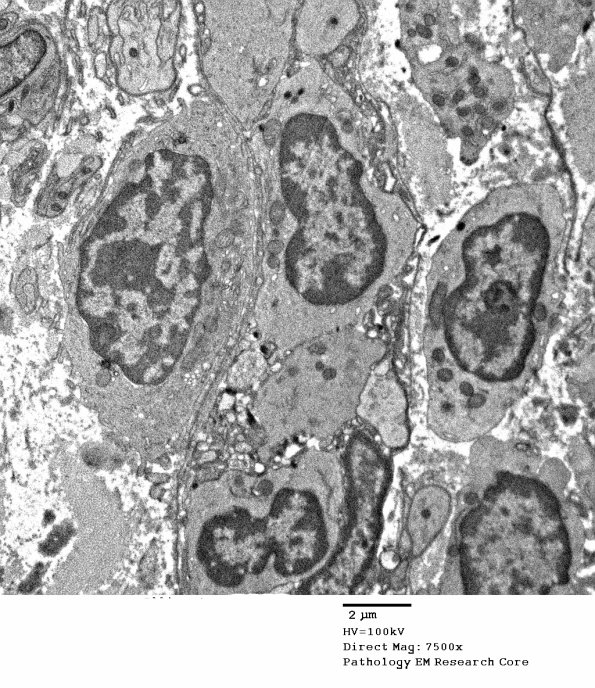

Additional epithelioid histiocytes. (electron micrograph)